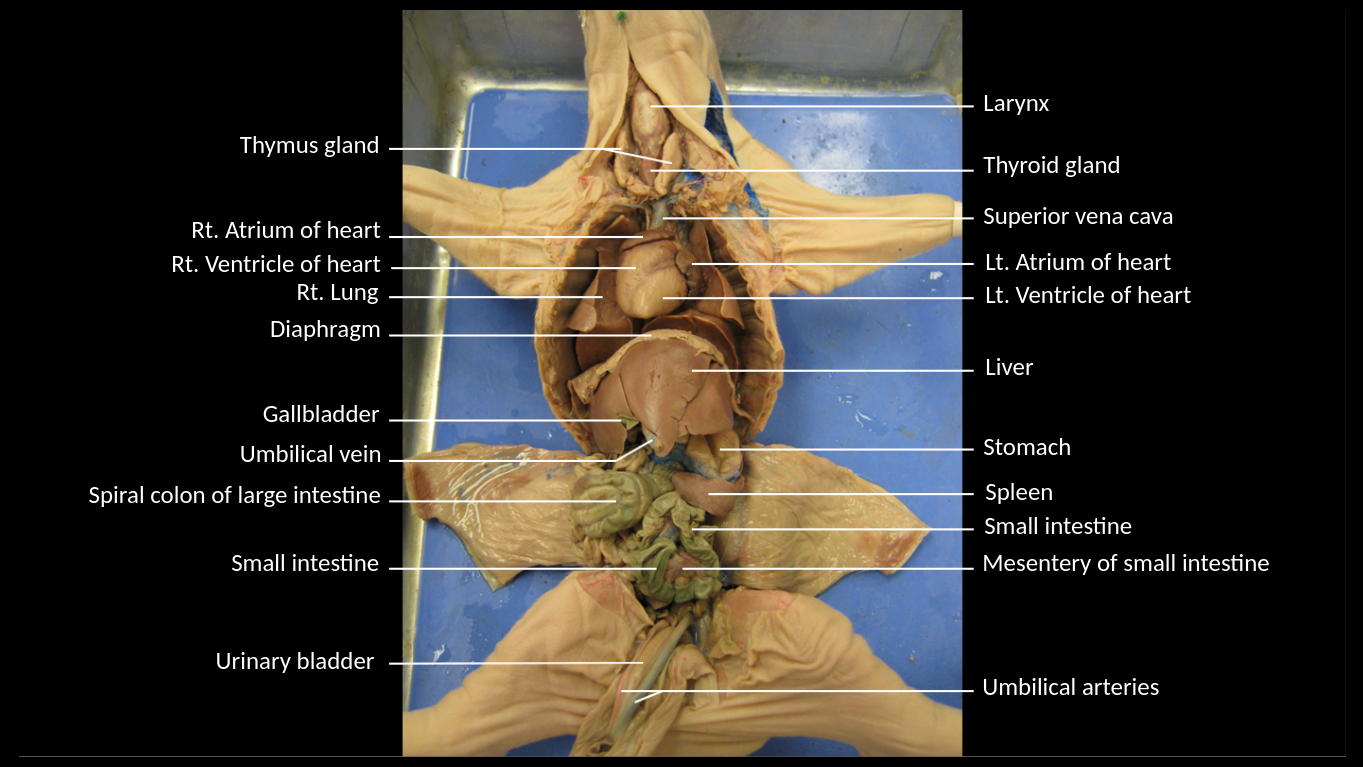

Areas of diffuse lymphatic tissue are found in the walls of the structures marked by the green arrows. They are called the///small intestine